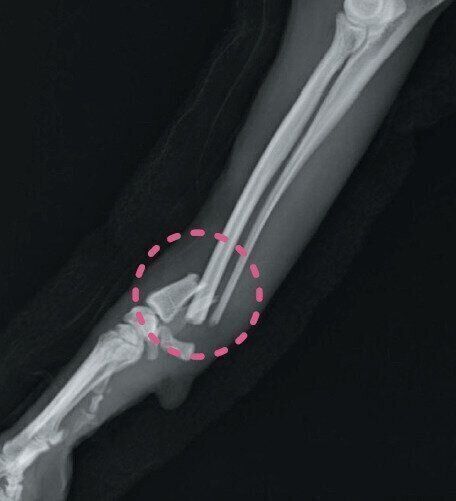

冬の骨折・脱臼(だっきゅう)

骨折や脱臼は季節に関係なく起きますが、冬ならではの理由で発症するものもあります。発症すると多くの場合で激しい痛みを伴います。積雪や道の凍結のほか、来客が増える年末年始など、次のようなシチュエーションに注意してください。